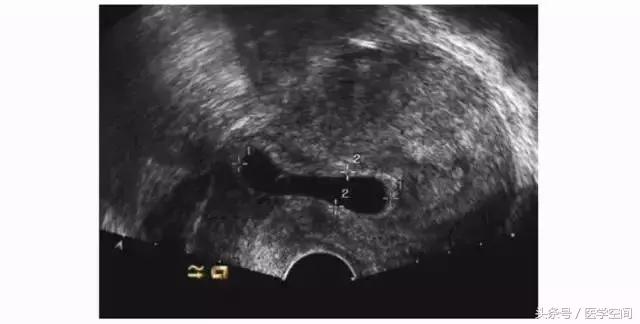

3.1CSP超声漏诊的原因及临床后果

孕囊部分着床于剖宫产子宫瘢痕处而孕囊主要位于宫腔内的不典型CSP(见图4)易被轻忽,这类CSP常常被当成了正常宫内早孕,有出血症状时会被认为是先兆流产,对这类患者进行药物流产或人工流产常会导致阴道淋漓出血或大出血需急诊手术干预治疗,有时不得不切除子宫。

图4不典型CSP的超声表现